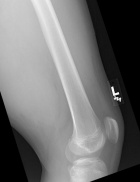

J.G. - 14 year old male c/o left posterior thigh mass for eight months. His mother noticed the mass, but no ecchymosis, after he fell while running hurdles. He complains of pain only when running long distances, and with prolonged pressure. It has decreased in size only minimally. No F/C.